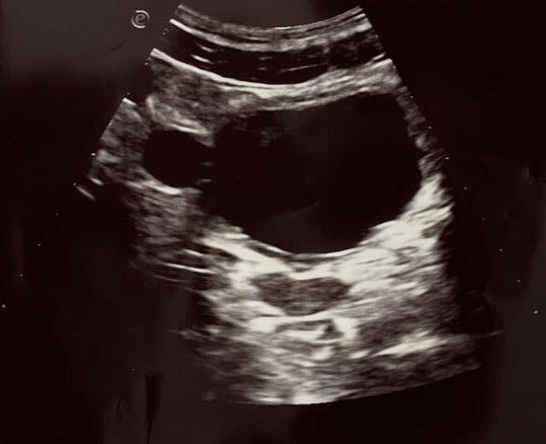

Hallazgos ecográficos

Imagen anecoica con bordes bien definidos, redondeada, de unos 19 mm de diámetro, localizada en la pared lateral derecha de la vejiga urinaria compatible con divertículo vesical extramural.